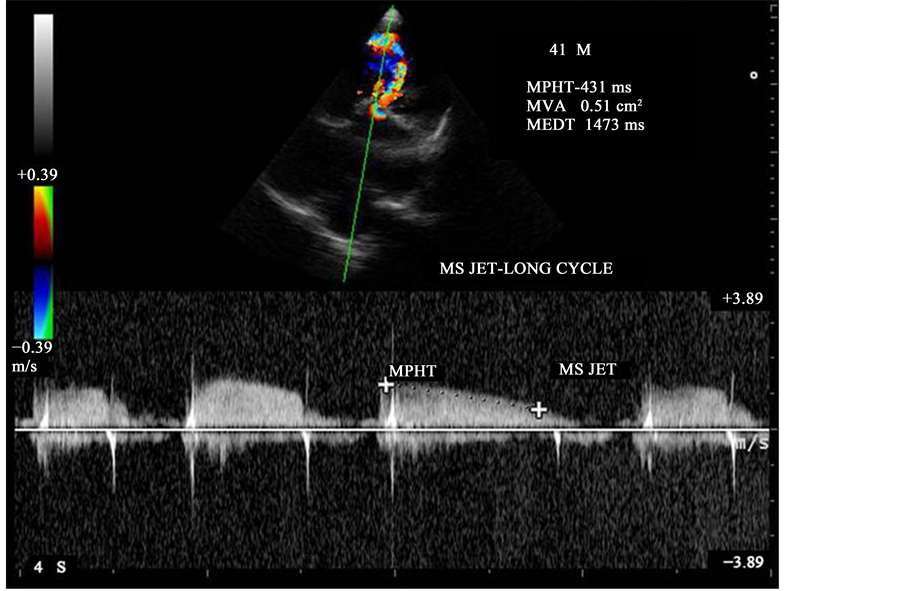

Figure 25. CW doppler showing the MS jet-long cycle pressure half-time.

3.11. Pressure Half-Time

It is defined as the time interval in milliseconds between the maximum mitral gradient in early diastole and the time point where the gradient is half the maximum initial value. The decline of the velocity of diastolic transmitral flow is inversely proportional to valve area (cm2) and MVA (mitral valve area) is derived by using the empirical formula (MVA = 220/T1/2) [55] . The empirically determined constant of 220 is in fact proportional to the product of net compliance (i.e., the combined compliance of left atrium and LV) and the square root of maximum transmitral gradient in a model that does not take into account of active relaxation of LV [56] . In patients with Atrial Fibrillation, tracing should avoid mitral flow from short diastoles and average different cardiac

cycles as shown in Figure 25 and Figure 26, the mitral valve pressure half-time = 431 ms and Mitral valve area is 0.51 cm2 in long cycle and 443 ms and 0.50 cm2 in short cycle.

Aortic regurgitation causes the left ventricular pressure to increase more quickly in diastole than would otherwise occur. This can lead to shortening of pressure half-time and an underestimate of mitral stenosis severity. Early diastolic deceleration is prolonged when LV relaxation is impaired while it tends to be shortened in case of decreased LV compliance [57] . Rapid decrease in mitral velocity flow, i.e., short T1/2 can be observed despite severe MS in patients who have a particular low atrial compliance [58] . The deceleration slope is sometimes bimodal, the deceleration of mitral flow velocity being more rapid in early diastole than during the following part of the E-wave and in such cases, the deceleration slope in mid-diastole rather than the early deceleration slope be traced [59] . Planimetry is considered as the reference measurement of mitral valve area (MVA) [60] . The mitral valve areas measured by pressure half-time is 0.51 cm2 and 0.50 cm2 as shown in Figure 25 and Figure 26 are not correlated well with planimetry measurements as shown in Figure 20 (0.98 cm2) and 0.71 cm2 in Figure 21. The difference in planimetry measurements is due to positional variations, the point at which the orifice is planimetered [61] . Assessment of valve area using continuity equation and PISA (proximal isovelocity surface area) method are not recommended for routine use.